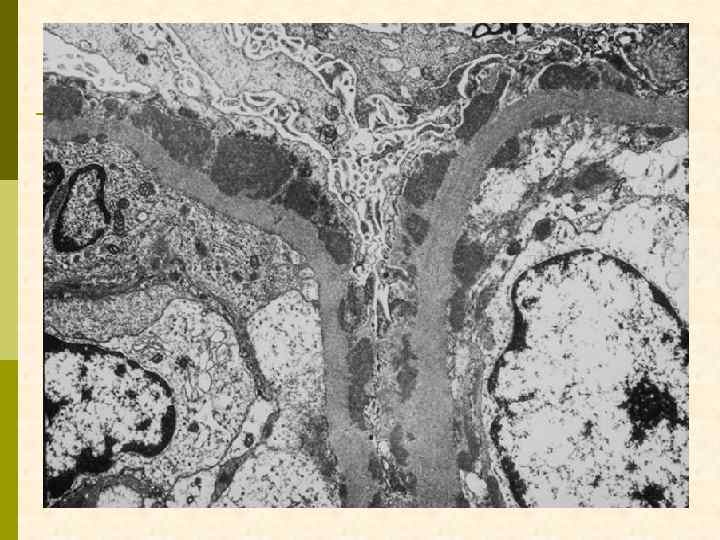

ХРОНИЧЕСКАЯ ТРОМБОТИЧЕСКАЯ МИКРОАНГИОПАТИЯ Ранние признаки: набухание эндотелиоцитов, потеря фенестр, отделение эндотелия от мембраны, заполнение субэндотелия электронно-прозрачным материалом (белки, участвующие в процессе свертывания + клеточный детрит), новообразование базальных мембран под смещенным эндотелием. Нефробиоптат больного первичным антифосфолипидным синдромом